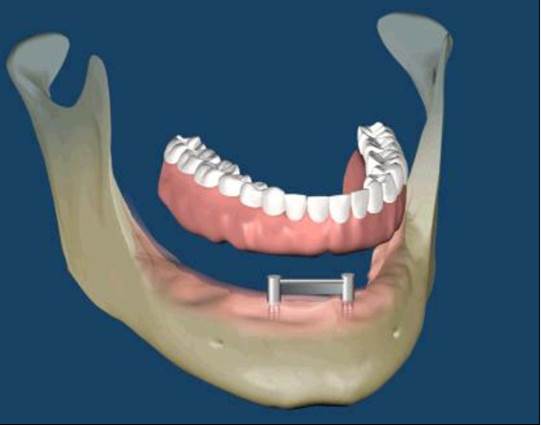

All-on-Fou/Six

近年來由於人工植牙的技術普及,患者大都知道植牙可做固定式假牙,但同樣的有時患者因為身體、經劑因素等受限,也可以考慮植入幾支人工植牙,再完成固定可撤式活動義齒,這樣可讓活動式假牙的固定性有效加強。通常上顎可用6支植體,下顎則4-5支植體固定,如需更穩定的受力,亦可再增加植體數目。(圖52-55)